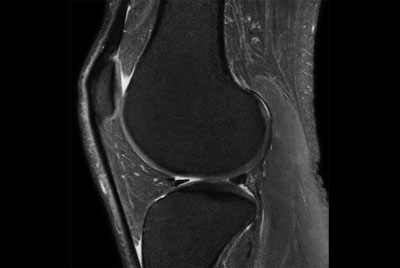

SmartSpeed Traumatic Knee imaging

SmartSpeed 2 min Knee imaging

Knee imaging with Compressed SENSE

Knee exam with/without Compressed SENSE